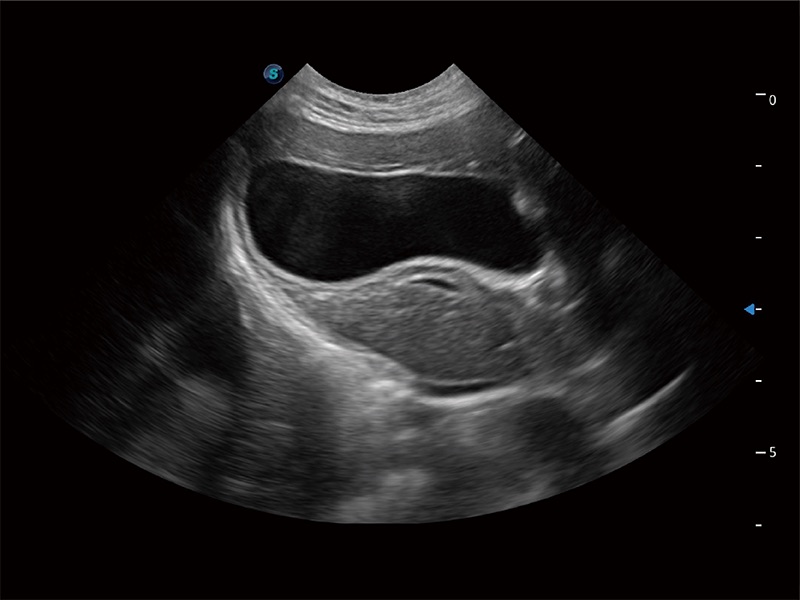

优异的基础图像

ProPet 80 全新的动物超声智能软件和丰富的探头群,为动物医生提供了高清晰度和精细分辨率的图像,无论在宠物、马科、畜牧还是实验室动物等应用中都可以轻松应对,为您的日常工作带来满意的体验。

(猫)胆囊